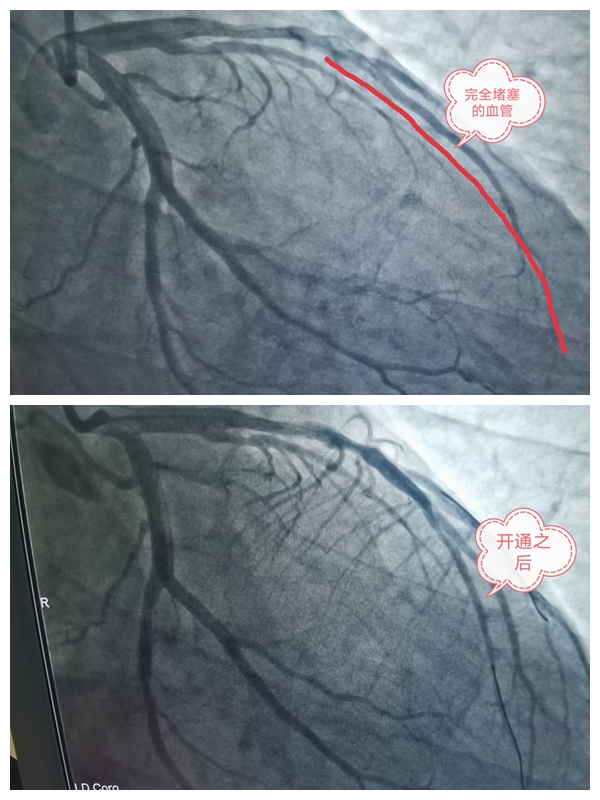

我院立即启动胸痛中心救治系统,开通绿色通道,口服心梗一包药,迅速组织救援团队,积极做好急诊手术准备。心内科手术医师在接到通知后在短短15分钟内全部到位,准备就绪,患者造影结果显示:前降支完全堵塞,可见明显血栓,快速置入导丝、球囊,冠脉内注入抗栓药物,迅速打开闭塞血管,使梗死血管血流通畅,恢复患者血运循环,患者胸痛症状立马消失。

胸痛中心团队仅用40分钟就顺利完成该例急诊介入手术,显著低于胸痛中心要求的90分钟。手术非常成功,术后患者几乎没有不舒服的感觉,患者转危为安,平安送回心内科ccu病房监护,分秒必争的救治为患者赢来了最佳治疗时机,为患者赢来了“二次生命”。